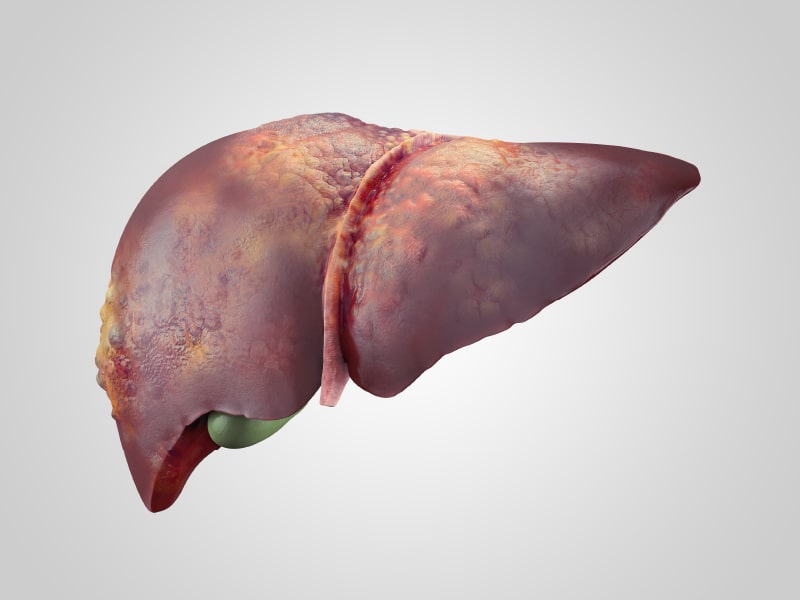

Son nódulos o crecimiento anormal de células que crecen en el hígado, y estos pueden ser benignos (no cancerosos) o malignos (cáncer). Los tumores hepáticos benignos son relativamente frecuentes y no suelen producir síntomas. Sin embargo, en muy pocas ocasiones algunos de estos tumores provocan malestar en la zona derecha superior del abdomen, o causan un aumento del volumen del hígado. Entre los tumores hepáticos no cancerosos (benignos) se incluyen:

Los tumores hepáticos malignos se clasifican en primarios (que se originan en el hígado) o metastásicos (diseminados desde otra parte del organismo. El cáncer se extiende con frecuencia al hígado, dado que cuando las células tumorales se separan de un tumor maligno localizado en otra parte del organismo, con frecuencia se introducen en el torrente sanguíneo y viajan por él, y es precisamente el hígado el órgano que filtra la mayor parte de la sangre procedente del resto del organismo.

Entre los tumores malignos primarios más frecuentes son el hepatocarcinoma o carcinoma hepatocelular y el colangiocarcinoma intrahepático. Estos tumores tienen una elevada mortalidad si no son diagnosticados a tiempo para realizar un tratamiento oportuno.

El hepatocarcinoma crece generalmente en un hígado con cirrosis, la misma que puede ocasionarse por múltiples factores, como esteatosis hepática alcohólica o no alcohólica, virus de la hepatitis B y C, alcohol, tóxicos, enfermedades autoinmunes, entre otros.